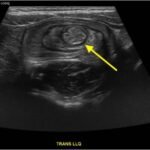

Intussusception is the telescoping of bowel into an adjacent segment of bowel and has an associated risk for bowel ischemia and perforation. The classic triad of abdominal pain, blood in stool, and an abdominal mass is present in less than 40% of pediatric cases and is less common in older children.1 Ultrasound has a high sensitivity and specificity for the diagnosis of intussusception, and once diagnosed, treatment modalities include reduction by either ultrasound or fluoroscopic guided air or hydrostatic enema. The risk of recurrence after successful reduction occurs in up to 12% of pediatric patients and occurs more frequently in older children and children with a pathologic lead point.2 We present a case of a 6-year-old child with colocolic intussusception that was successfully reduced and recurred within five days due to a large colonic polyp.